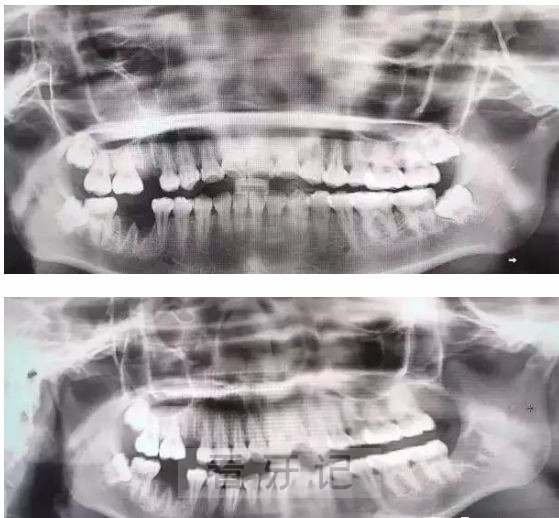

拔牙费用一万多的牙齿长什么样? 2024年8月3日 23:13 • 最新动态 上面这两张图,据说拔牙费时1.5小时,收费14000元,也不知道是真是假。 由于智齿的生长位置特殊,导致了拔除难易不同,如智齿出现横着长或者靠近牙神经的话,则难度会较高,一般人只需拍个口腔全景片,但相对于智齿靠近神经管的情况,还可能需要拍CT,这都很考验牙医的技术。 本文内容源自网络仅供参考,不作为诊断医疗依据,更多查询请 → 在线咨询客服 相关推荐 最新动态 杭州种牙十大口腔医生名单前十名单:关呈超、蒋贤军、章峥等 很多人种牙都会想着去**口腔、省口这种**专科医院,但是超长预约时间和专家费高价格把想法给打回原形。今天来看看杭州私立种植牙医生排名人气前十都是杭州牙友推荐的口碑种牙医生! 1、关… 2024年6月20日 最新动态 安阳公朴口腔医院2025年春节放假时间出炉!初六正常开诊上班 【安阳公朴口腔医院】蛇年大吉,平安新年—2025年春节放假通知 1月27日(农历二十八、周一)至2月2日(农历正月初五周二)放假调休,共7天。 1月26日(周日)、2月3日(农历正… 2025年1月22日 最新动态 刚刚!柏乐口腔召开2025年10月医疗工作会议!深化质控体系建设推动医疗技术高质量发展 10月15日,柏乐口腔2025年10月医疗工作会议在南湖总院召开。会议由柏乐口腔医政医管部总监叶常青主持,柏乐口腔执行总裁唐建清、南宁事业部副总经理王清海、医疗总院长彭布强等管理层… 2025年10月20日